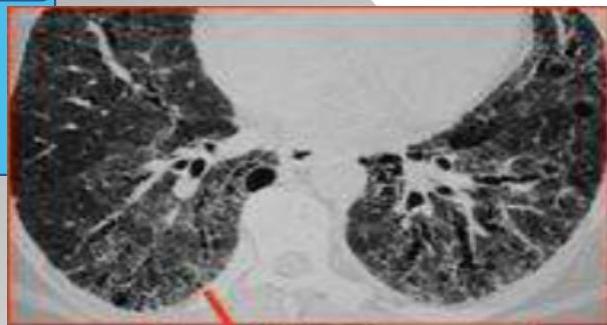

Signet Ring Appearance

CT scan showing bronchiectasis. Note the dilated bronchi with thickened wall, which are larger than adjacent arteries, giving a signet ring appearance.